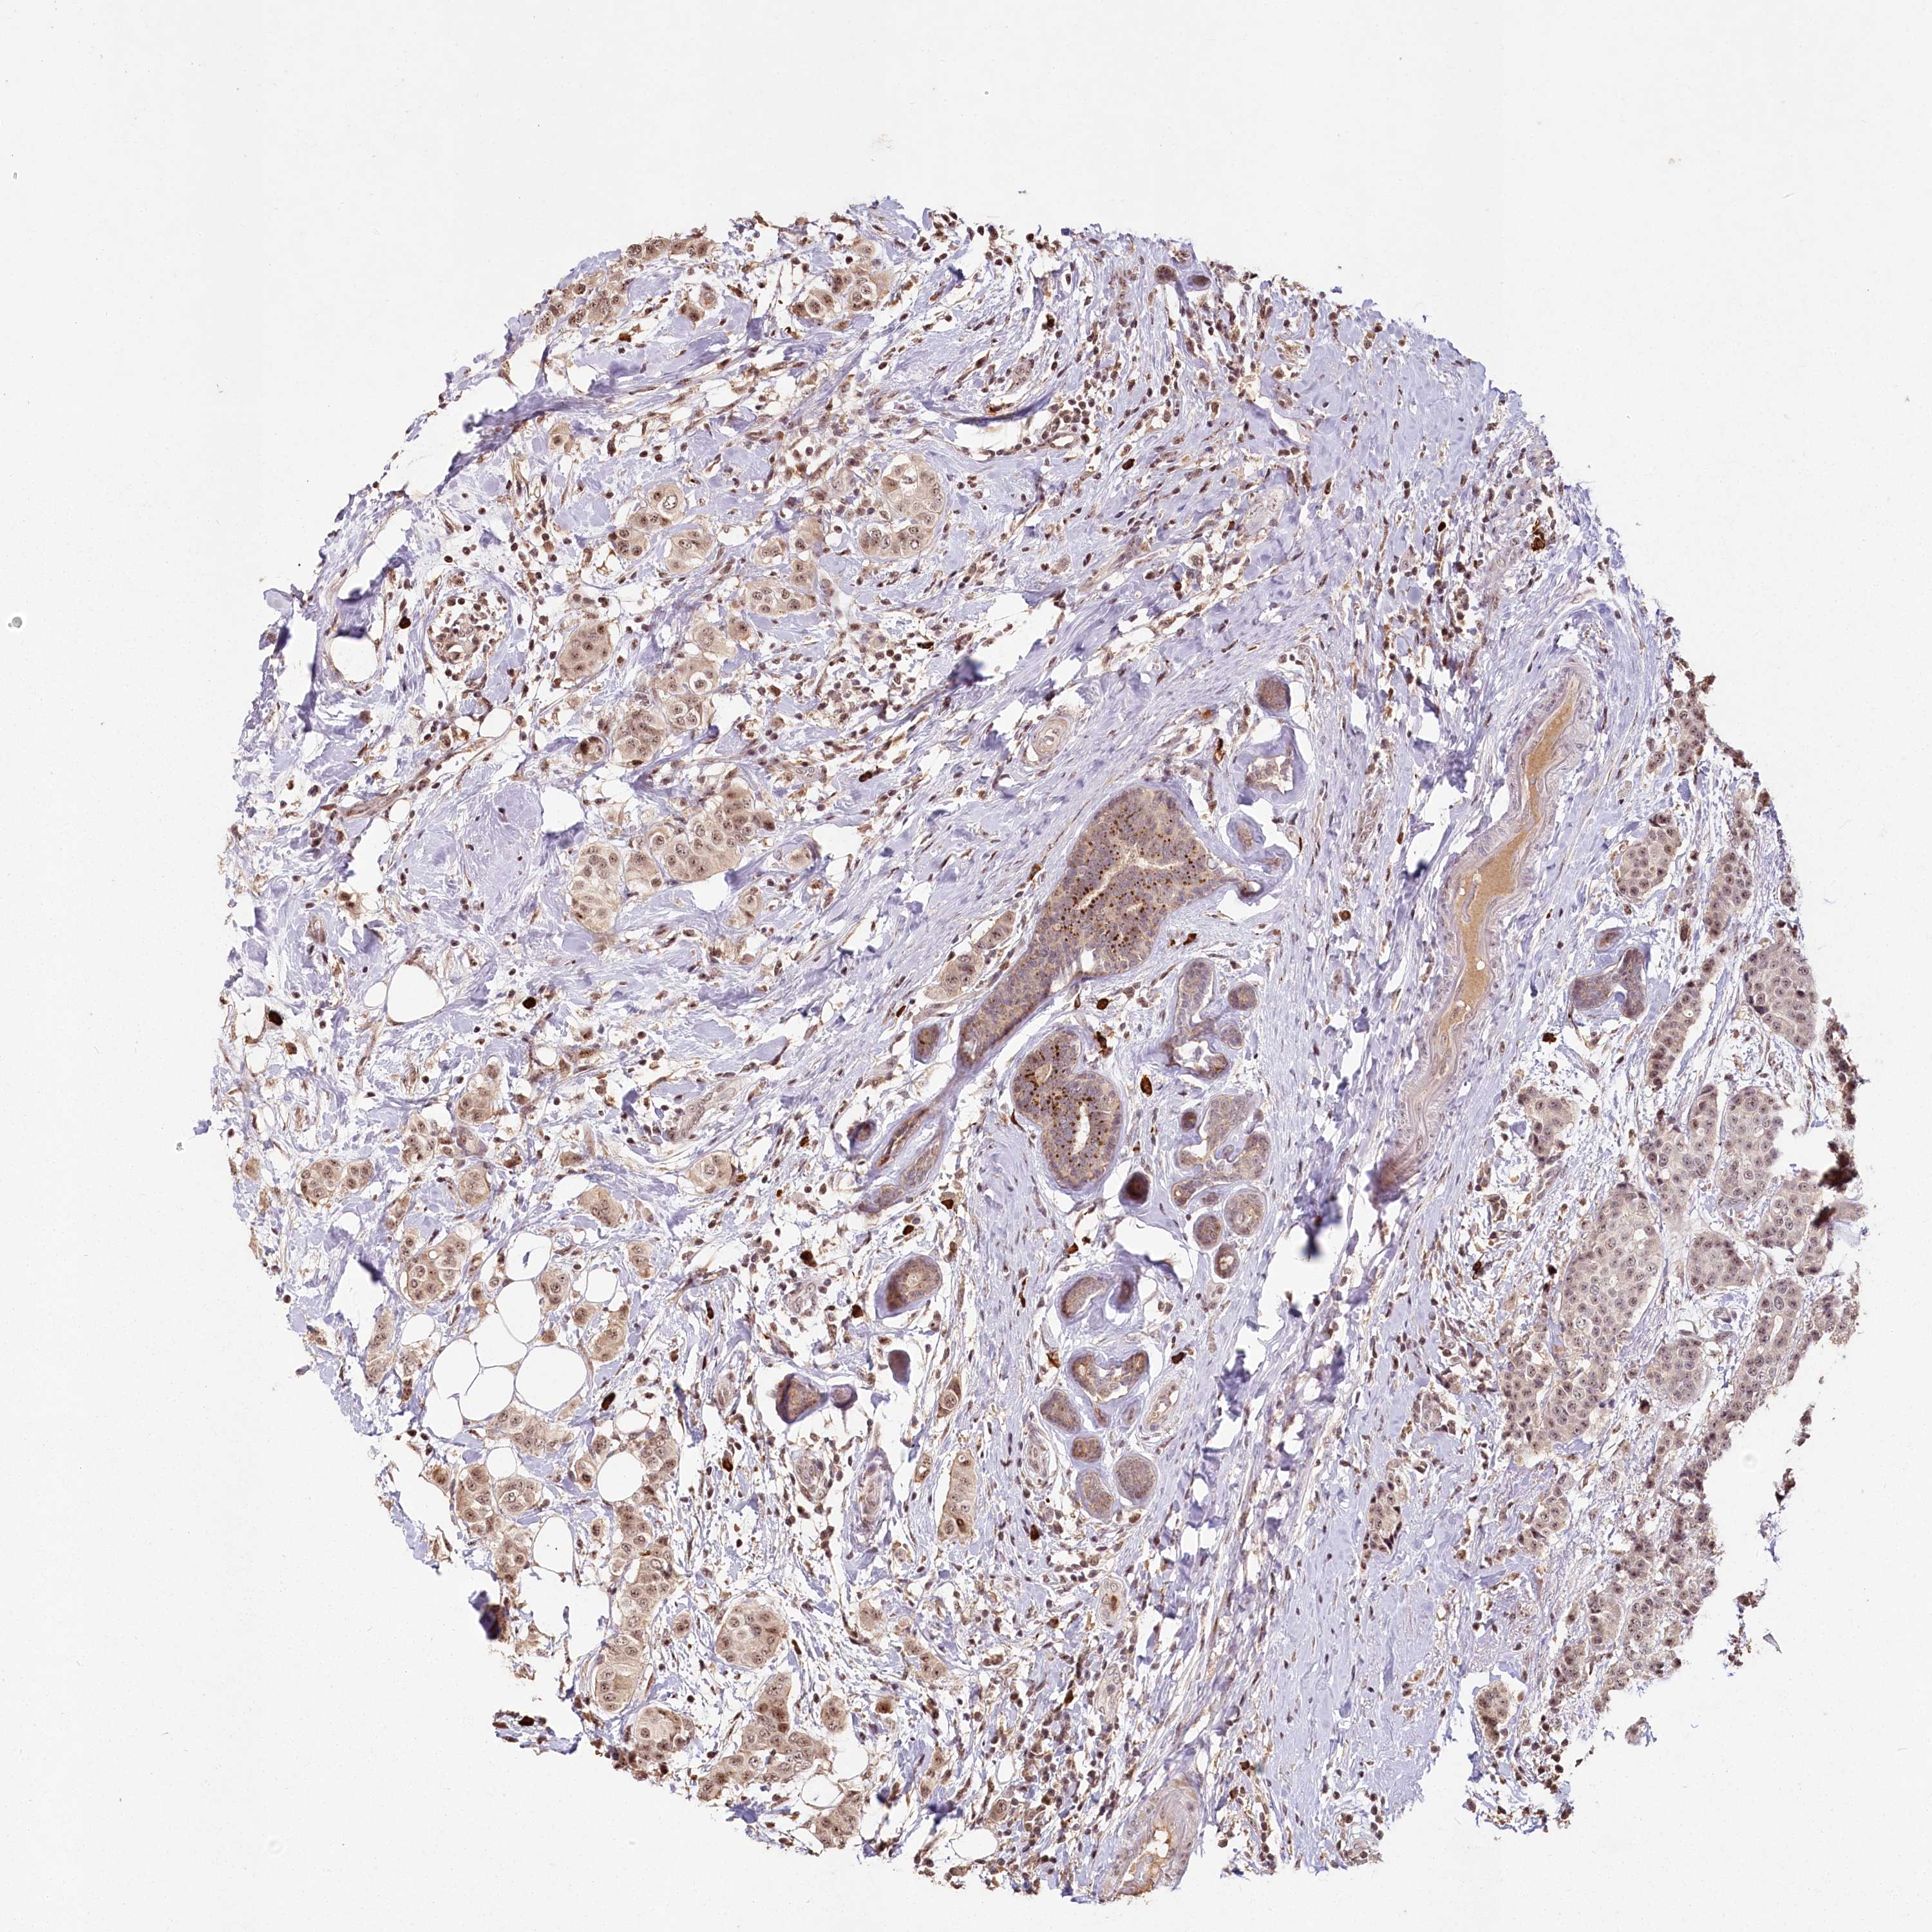

BRCA TCGA BRCA VALIDATION PROTEIN EXPRESSION

ANTIBODIES

AND

VALIDATION